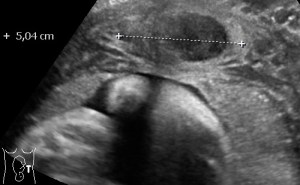

Multiple Myomas in pregnancy 1